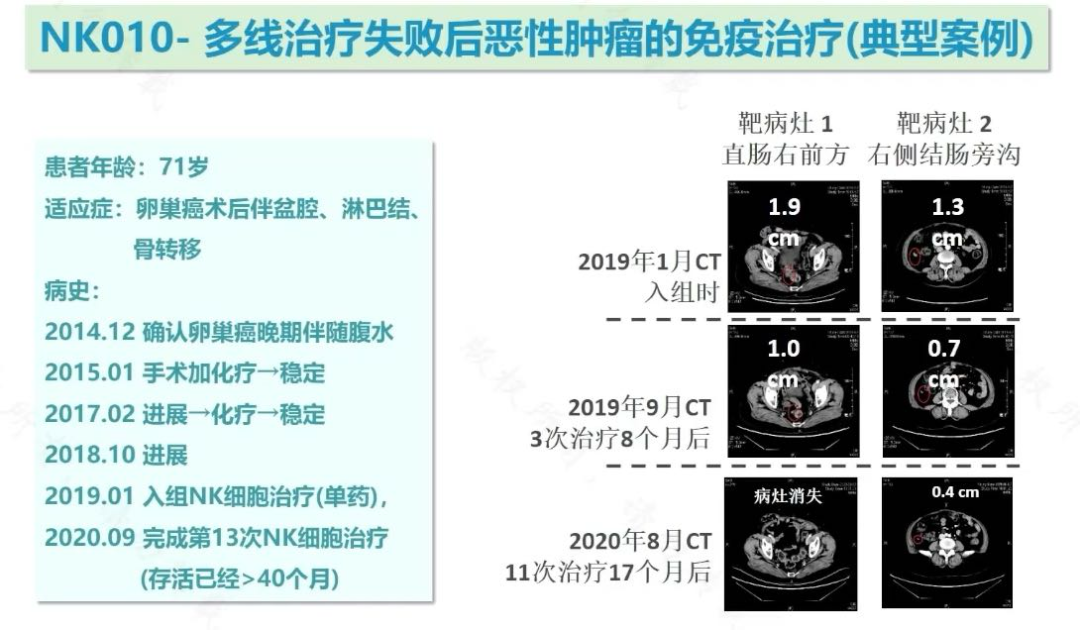

在针对NK010的临床试验中,多名预计生存期仅2-6个月的铂耐药晚期卵巢癌患者,通过NK细胞治疗显著延长了生存时间。

其中一位患者的故事尤为鼓舞人心。该患者于2014年确诊晚期卵巢癌,历经手术、化疗,病情仍不断进展。2019年入组NK细胞治疗临床研究时,体内已有多个转移病灶。经过13次NK细胞治疗,截至2020年9月,患者已存活超过40个月,且影像学检查显示病灶明显缩小甚至消失。